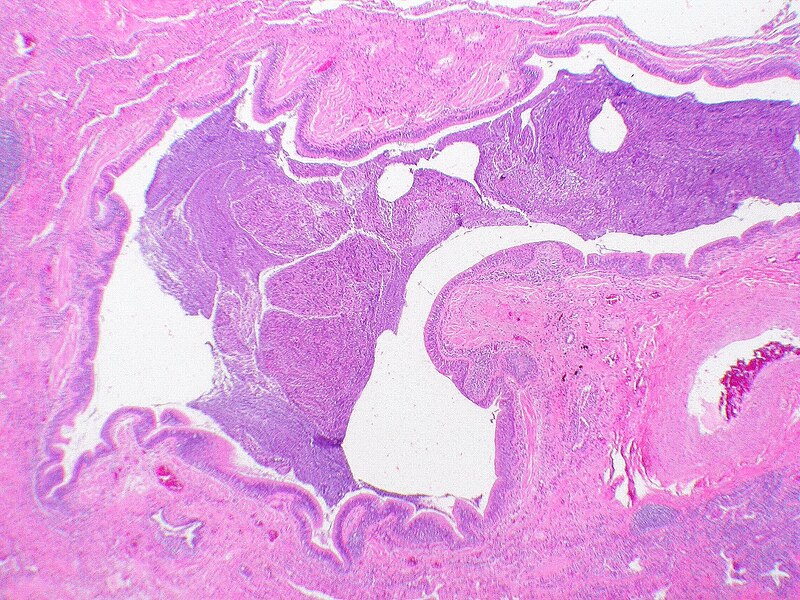

For distinction from neonatal respiratory distress syndrome, acute respiratory distress syndrome was also labelled as adult respiratory distress syndrome (ARDS). It involves inflammation in the lung parenchyma, increased alveolar permeability, reduced lung compliance and non-functional gas exchange. The increased alveolar permeability allows fluid to build up which in-turn prevents the lungs from filling up air, causing less oxygen in the bloodstream. The oxygen deprivation sequentially leads to organ failure. Low blood-oxygen levels in the bloodstream not only affects the lungs but, also harms other organs in the body and prevents oxygen from reaching them for normal functioning. The intensity of the disease can be determined by measuring and comparing blood-oxygen levels. ARDS is a rapidly developing and potentially fatal lung disease, most people don’t survive ARDS. ARDS survivors mostly have lasting damage to their lungs. The risk of death and the severity of the disease increases with age. The main symptom of ARDS is distressing shortness of breath, which develops within the first couple hours and lasts longer than the illness and the duration of recovery.